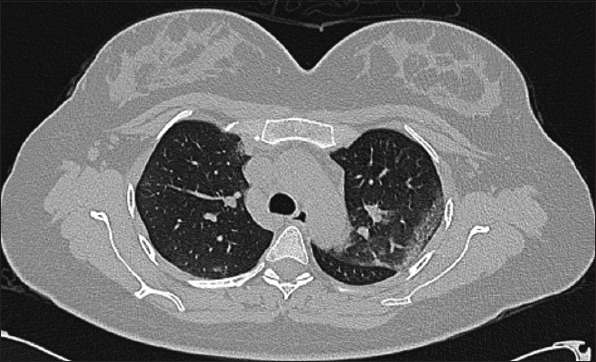

Results: A total of 31 case reports (level of clinical evidence: IV) of AAC related to COVID-19 were included. The mean age of patients was 64.7 ± 14.8 years, with a male-to-female ratio of 2.1:1. Major clinical presentations included fever 18 (58.0%), abdominal pain 16 (51.6%), and cough 6 (19.3%). Hypertension 17 (54.8%), diabetes mellitus 5 (16.1%), and cardiac disease 5 (16.1%) were among the common comorbid conditions. COVID-19 pneumonia was encountered before, after, or concurrently with AAC in 17 (54.8%), 10 (32.2%), and 4 (12.9%) patients, respectively. Coagulopathy was noted in 9 (29.0%) patients. Imaging studies for AAC included computed tomography scan and ultrasonography in 21 (67.7%) and 8 (25.8%) cases, respectively. Based on the Tokyo Guidelines 2018 criteria for severity, 22 (70.9%) had grade II and 9 (29.0%) patients had grade I cholecystitis. Treatment included surgical intervention in 17 (54.8%), conservative management alone in 8 (25.8%), and percutaneous transhepatic gallbladder drainage in 6 (19.3%) patients. Clinical recovery was achieved in 29 (93.5%) patients. Gallbladder perforation was encountered as a sequela in 4 (12.9%) patients. The mortality rate in patients with AAC following COVID-19 was 6.5%.